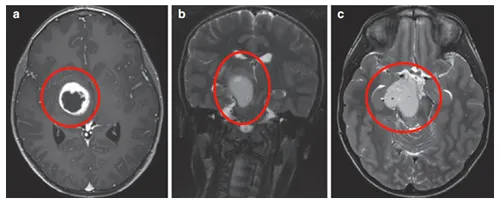

MRI显示右侧丘脑存在环形强化结节状肿瘤,累及内侧颞叶结构。

Rutka教授实施经颞中回-脑室入路次全切除术,病理证实为WHO I级毛细胞星形细胞瘤,BRAF重复融合、BRAF V600E及H3K27M检测均为阴性,基因检测检出NF1基因变异。

术后影像学随访显示丘脑部分切除及中脑残留病灶,遂制定个体化辅助放疗方案,患儿治疗反应良好。术后6个月复查确认肿瘤控制情况稳定。